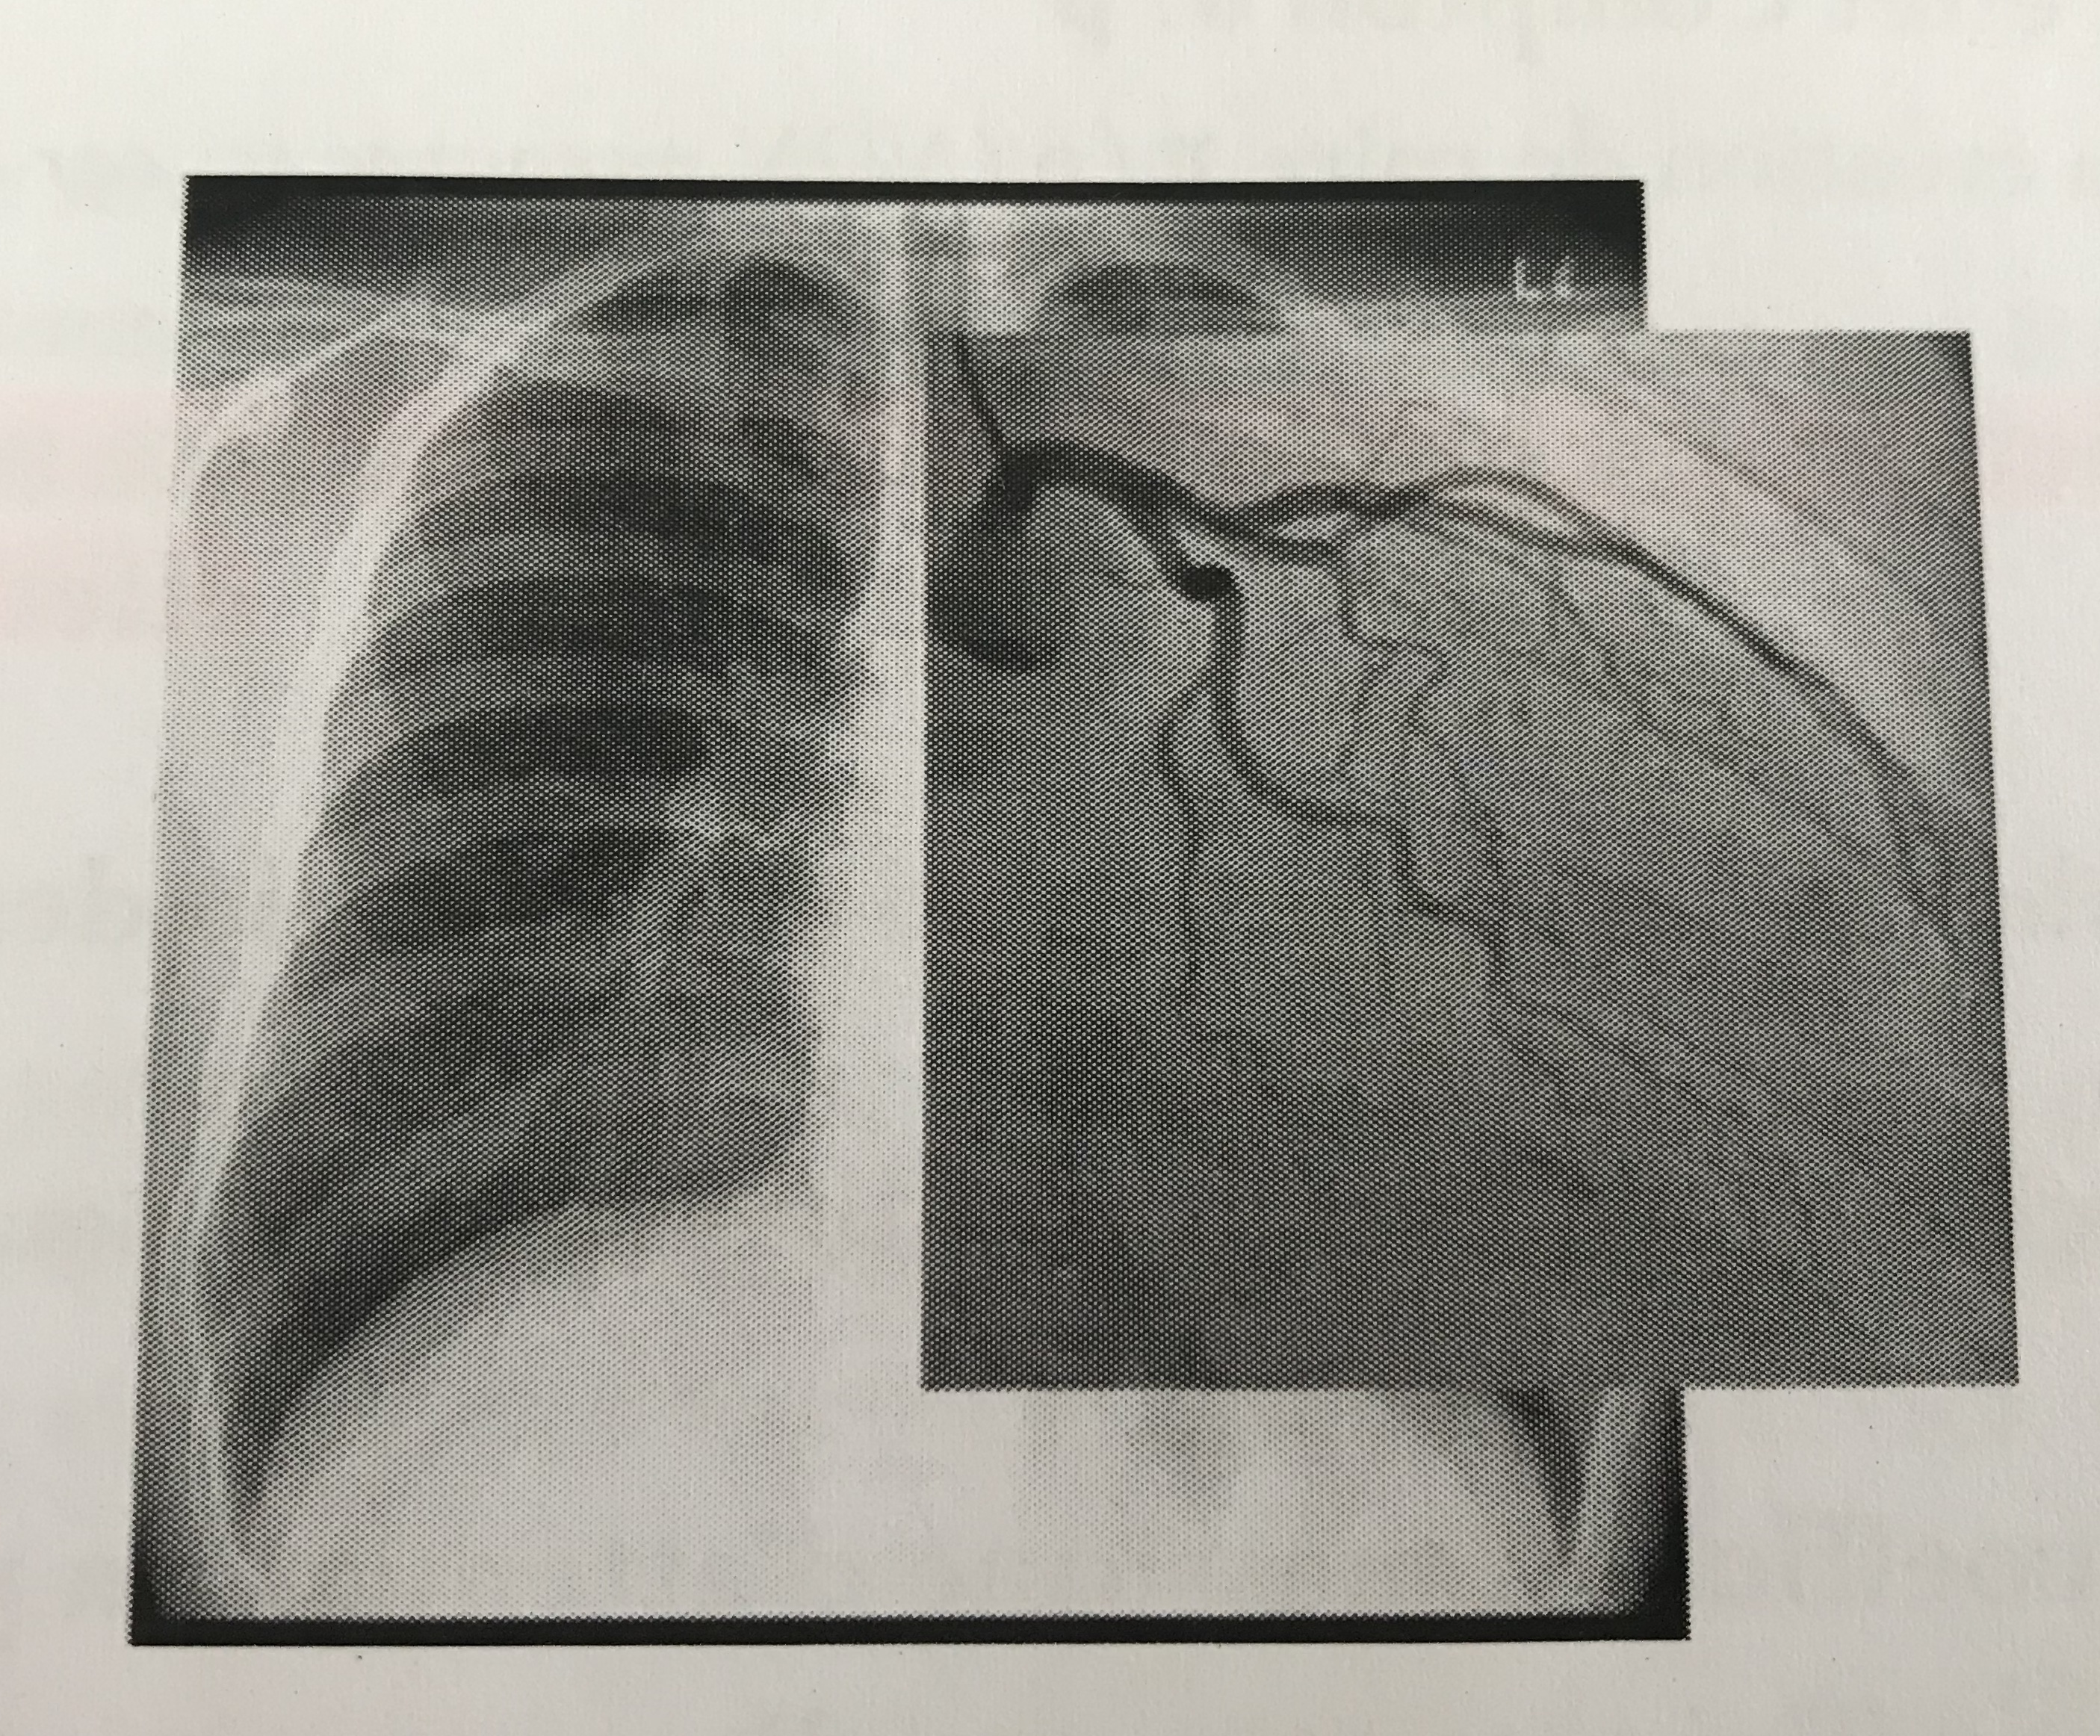

L'iode à un Z très élevé et un coefficient linéique d'atténuation encore plus important que les Os du coup les RX seront beaucoup plus atténués mais le problème c'est que les coronaires avec le contraste iodé apparaissent en noir alors que si j'ai bien compris plus c'est atténué par effets photoélectrique plus c'est blanc du coup je ne comprend pas trop.

Donc déjà tu sais que ton produit de contraste pour être efficace il faut qu'il soit très riche en électrons donc avec un Z important. Ainsi, il va atténuer de façon importante les RX par effet photo-électrique. Tu sais que grâce à un écran luminescent on va pouvoir changer la longueur d'onde des RX afin de les rendre visibles. Moi je me disais: ceux qui arrivent à traverser le patient, ils vont faire de la "lumière" du moins on va les voir donc ce sont les zones en blanc alors que les zones riches en électrons comme les os etc... on ne verra pas les RX car ils on été atténués (ils ne traversent pas les os) donc la zone apparaîtra noire. C'est comme dans un verre si tu mets de l'eau tu vois de l'autre coté: la lumière traverse l'eau sans être atténuée alors que si tu mets du coca elle sera plus atténuée donc elle traversera moins et donc on la verra moins de l'autre côté du verre. :wink2: Du coup quand tu mets l'iode dans le cas d'une coronarographie bah tu verras les coronaires en noir car l'iode a atténué les RX à cet endroit là étant donné qu'on l'a injecté dans les coronaires?